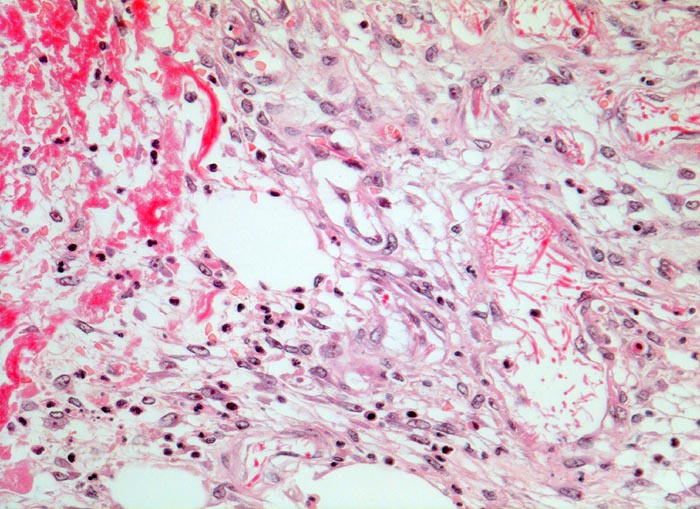

PathoPic ID 3574 - Wundheilung: Granulationsgewebe

Wundheilung: Granulationsgewebe

Entzündung / Reparatur

Haut, Rumpf

Haut

Lockeres, ödematöses Granulationsgewebe mit spindelförmigen

Fibroblasten und wenigen

neutrophilen Granulozyten. Links im Bild hellrotes Fibrin mit einzelnen neutrophilen Granulozyten.

6 Tage alte Wunde am Abdomen nach Laparotomie.

Histologie

320